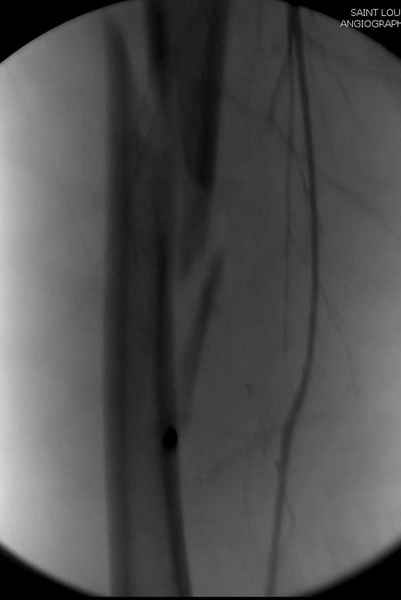

Второй случай тоже репозиция из малого доступа, больному 19 лет, множественные огнестрельные повреждениия конечностей, живота и черепа, правая конечность холодная, без пульсации. Ортопедический диагноз: огнестрельный перелом правого бедра. При срочной ангиографии повреждения сосудов не подтвердилось, конечность из-за ургентности состояния больного зафиксирована временным наружным фиксатором и больной оставлен на операционном столе для срочной лапаротомии хирургической службой.